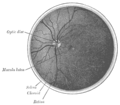

Fundus photographs of the right eye (left image) and left eye (right image), seen from front so that left in each image is to the person's right. The gaze is into the camera, so in each picture the macula is in the center of the image, and the optic disk is located towards the nose.